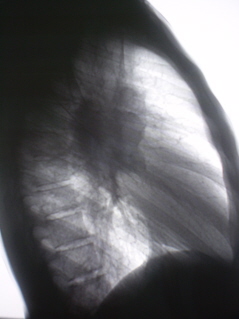

Цифровое стандартное флюорографическое профилактическое исследование (проведено на цифровом флюорографе «Ренекс – Флюоро»). На цифровых флюорограммах, произведенных в прямой, правой и левой боковых проекциях с обеих сторон определяется синдром двусторонней аденопатии. С обеих сторон определяется резкое увеличение и гомгенизация тени корней за счет резко гиперплазированных, в основном, бронхопульмональных лимфатических узлов с довольно чёткими, ровными контурами. Структура тени однородная. На фоне гиперплазированных лимфатических узлов чётко дифференцируются просветы главных бронхов.

Иллюстрации 1, 2, 3.